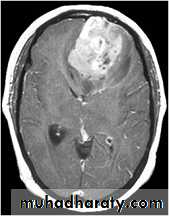

Secondary metastasis

Old age group above 50 Y , any lesion within the cerebellar hemisphere it is secondary metastasis unless proven otherwise F. from breast CA M. from bronchogenic CA .

Appear as nodular single or multiple lesion hypo dense or hyper dense .

Surrounded by per focal edema

Enhanced as solid or ring pattern of enhancement .